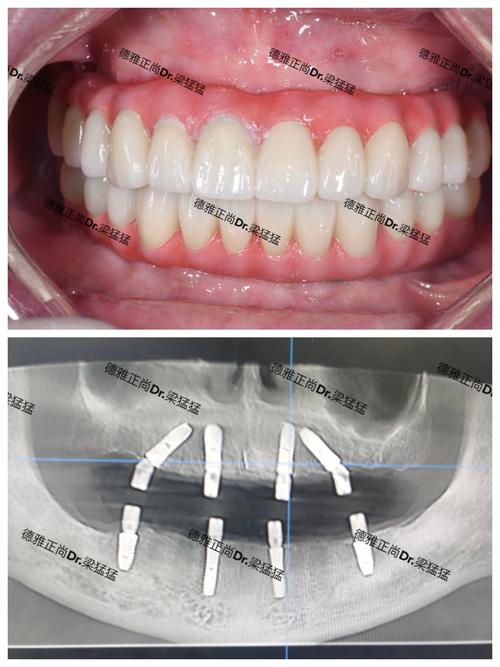

- 半口/全口牙缺失患者:通过All-on-4或All-on-6技术,用4-6颗种植体支撑半口或全口牙桥,避免传统活动假牙的异物感和不适;